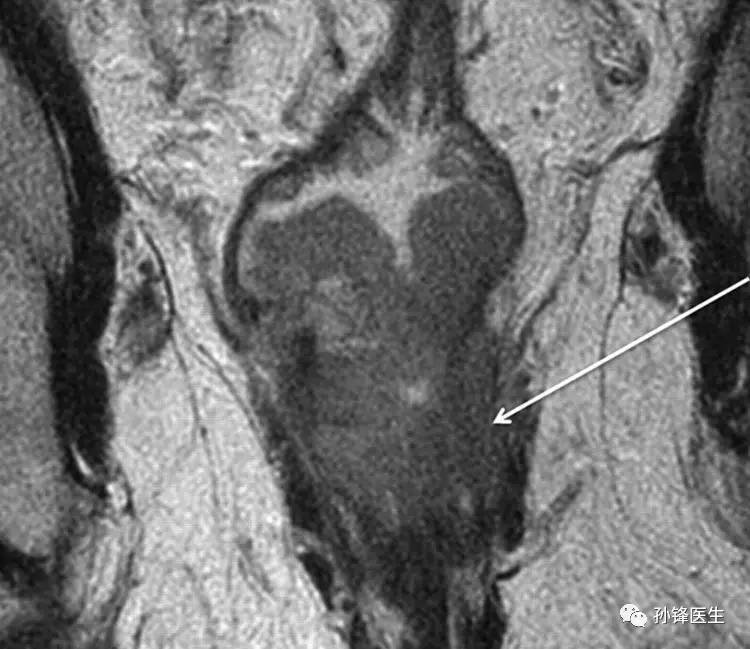

【例6】:58岁低位直肠癌男性, T2加权冠状MR图像显示左侧入侵到内侧平面(箭头)。

医学干货︱手把手教你直肠的核磁共振(中):直肠癌的分期

MR图像的示意图(↓